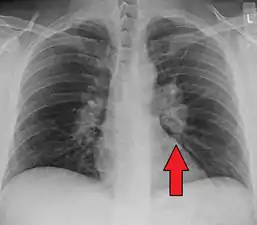

| Chest X-ray showing the typical nodularity of sarcoidosis, predominantly in the hila of the lungs. | |

Chest radiograph changes are divided into four stages:[105]

- bihilar lymphadenopathy

- bihilar lymphadenopathy and reticulonodular infiltrates

- bilateral pulmonary infiltrates

- fibrocystic sarcoidosis typically with upward hilar retraction, cystic and bullous changes

Although people with stage 1 radiographs tend to have the acute or subacute, reversible form of the disease, those with stages 2 and 3 often have the chronic, progressive disease; these patterns do not represent consecutive "stages" of sarcoidosis. Thus, except for epidemiologic purposes, this categorization is mostly of historic interest.[28]

Hilar adenopathy especially on the person's left (AP CXR)

Hilar adenopathy especially on the person's left (AP CXR) Hilar adenopathy especially on the person's left (lateral CXR)